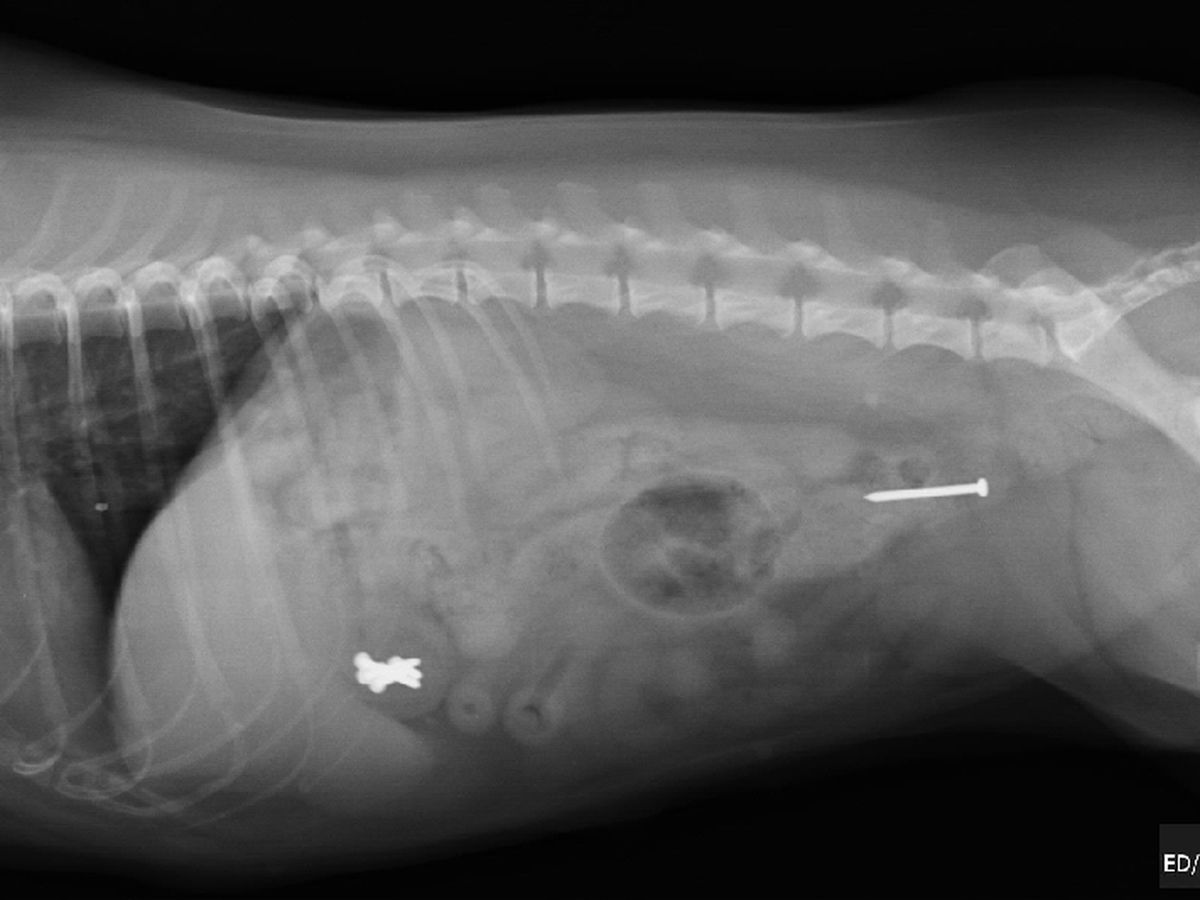

I then took Clarice to the vet for an Xray which revealed 6 nails stuck inside her stomach and 1 somehow luckily on its way out. The option to leave then in her stomach and hope for a safe exit is too risky due to the sharp nails possibly puncturing holes inside her body. Surgery is the only reasonable option.